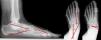

Description of therapeutic interventionCases were treated surgically by two experienced foot and ankle surgeons using a technique previously described in the literature.6,7 Under spinal anaesthesia, in prone and with tourniquet, a MDCO was performed through an oblique incision to expose the lateral wall of the calcaneus and correct the malalignment by displacing the tuberosity. Displacement of 10mm was determined intraoperatively using calcaneus long axials views and fixation was achieved through 2 headless compression screws (Fig. 1). Postoperatively, patients were placed in short leg cast without weightbearing for 4 weeks, followed by 4 weeks of rehabilitation with progressive range-of-motion and partial weightbearing to allow full weightbearing at 8 weeks postoperatively.

Radiographic outcomesAll included patients, performed at baseline and at one-year follow up AP and lateral weight-bearing radiographs. Those were measured to quantify the AP and lateral Talar-first Metatarsal angle (AP T-M1 and LAT T-M1), the AP and Lateral Talo-Calcaneal angle (AP TC and LAT TC) and the AP Talo-Navicular Coverage (TNC)12 (Fig. 2).